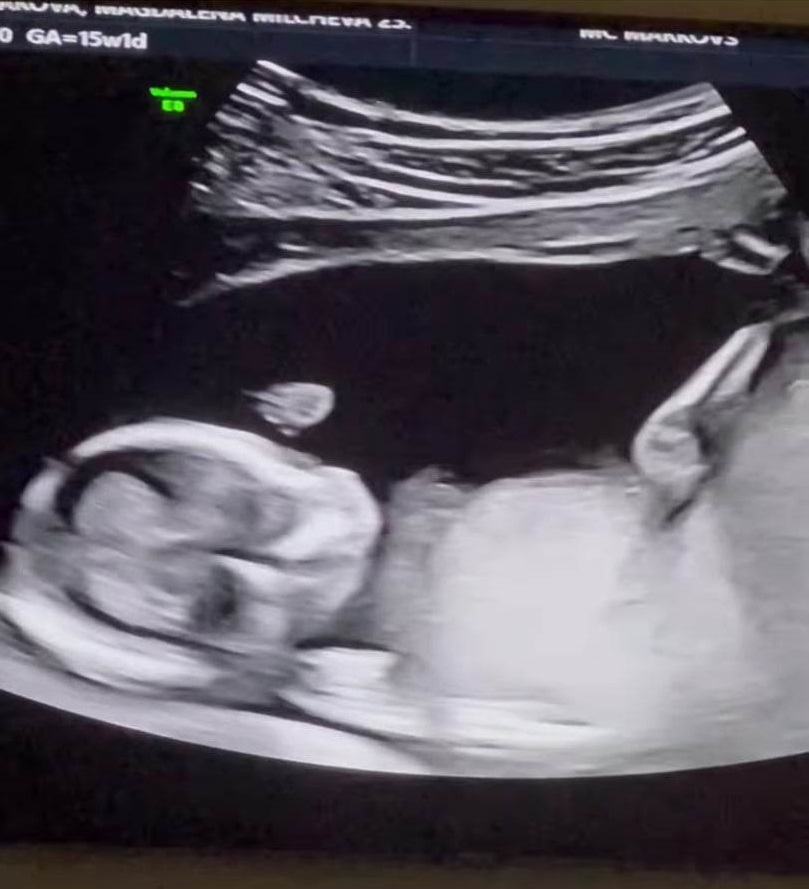

А в социалните мрежи гласовитата певица показа положителния тест и първата "снимка" на бебето – тази от ехографското изследване.